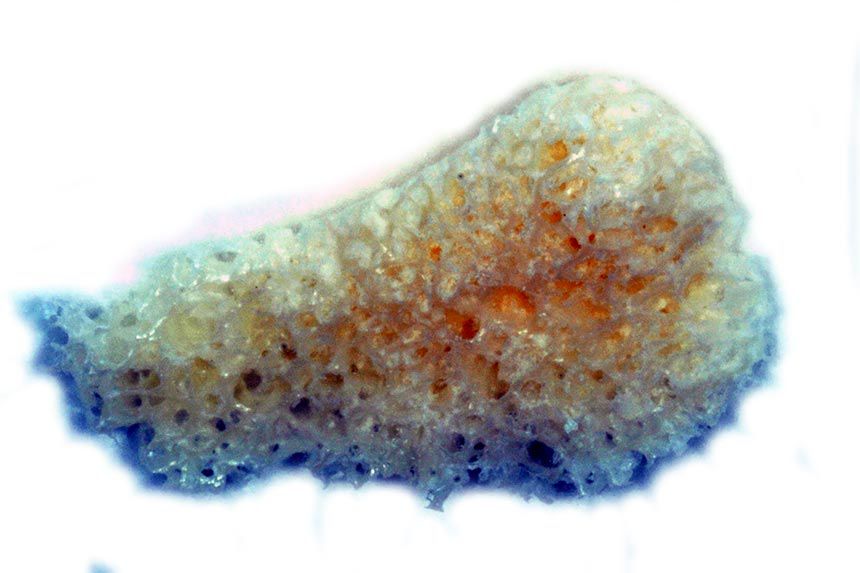

In order to obtain sufficient bone for the augmentation in the lower jaw and avoid any morbidity associated with iliac crest bone harvesting in this patient, we opted for the allogeneic bone augmentation technique proposed by the company botiss. The detailed planning included a CBCT scan and the virtual transmission of the ideal prosthetic arrangement of the lower jaw teeth (Fig. 5). The position of the implants was defined and the required bone material calculated. The data was then transmitted to botiss, who prepared our custom-made blocks from bone tissue (Fig. 6).